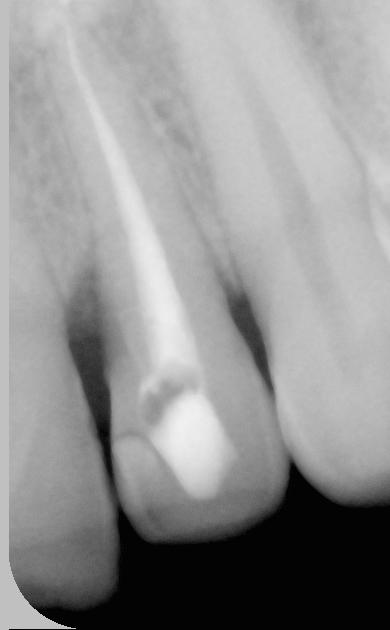

Un patient de 46 ans se présente au cabinet dentaire connaître les

possibilités de restauration esthétique de sa 22 sachant que celle ci,

dévitalisée, a subi une décoloration grisâtre et présente une pallato-version et

donc un défaut d'alignement sur l'arcade gênant le patient lorsqu'il sourit.

La dent est assymptomatique avec absence de lésion apicale. Le traitement

canalaire ne présente au sondage aucun soucis particulier au niveau de son

étanchéité